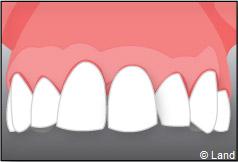

Situation clinique terminée